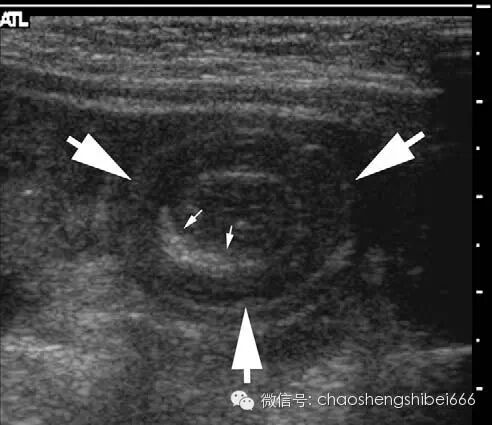

超声检查擅长于回结肠套叠的诊断,并且误诊较少。肠套叠通常表现为较大的肿块,肿块的直径接近100px甚至更大,肿块的长径长度取决于肠套叠的长度。虽然肿块能发生于腹腔及盆腔的任意位置,但多数肠套叠多发生于右中腹或者肝下间隙。因此超声检查应起始于右中腹,但是如果没有在右侧腹发现病变就要进行全腹扫查。根据作者的经验,阴性的超声检查结果具有很高的特异性。少数情况下,如果临床坚持怀疑存在套叠,可行钡灌肠检查。

回结肠肠套叠超声声像图上可见一个分层的肿块或可见肿块周边低回声的水肿的肠壁包裹(图6)。套叠内部中心的高回声是病灶内包裹的肠系膜脂肪,在其内经常可见淋巴结,多呈小于25px的椭圆形低回声结构(图7)。虽然没有超声检查征象可以肯定不能进行随后的钡灌肠治疗,但是超声检查的一些结果可以提示灌肠较难复位或容易合并穿孔。这些结果包括多普勒评价套叠的肠壁缺血以及肠套叠层那出现局限性积液。

6 4月大男婴肠套叠声像图呈低回声的面包圈征(箭头),中心 可见肠系膜脂肪强回声。L肝脏

7 3岁男孩肠套叠声像图(箭头),套入部肠系膜叠内可见多个发淋巴结(星号)